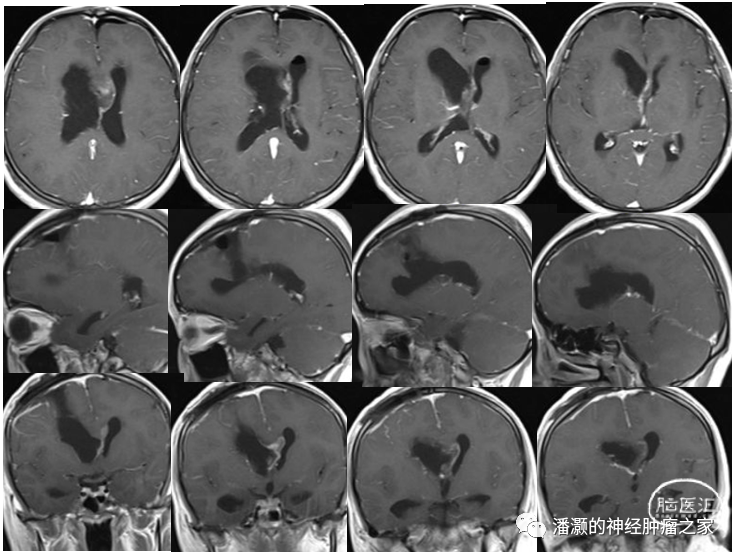

术后第三天复查头颅MR如下:

复查MRI提示两部位肿瘤均切除满意。未见明显肿瘤残留。